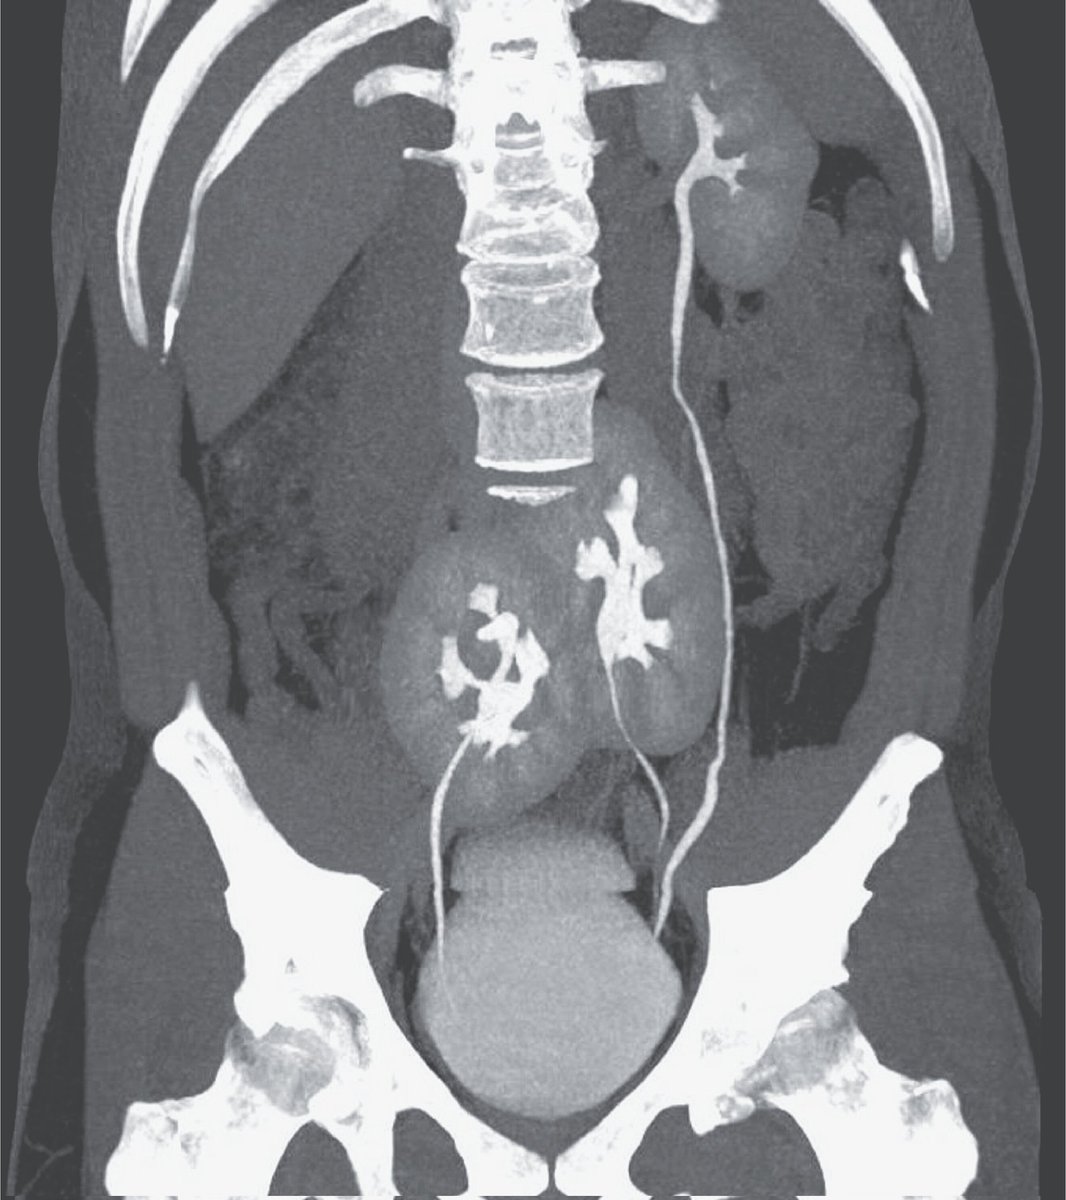

agora é só vender o terceiro rim e ficar com a grana

Médico: "Você ganhou na loteria biológica." Paciente: "Como assim?" Tomografia computadorizada: